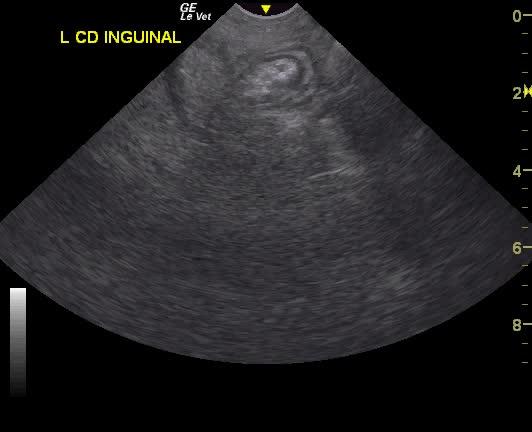

A NM Labrador with a history of foreign body ingestion was presented for intermittent diarrhea that had initially responded to bland diet, metronidazole and aminopentamide. More recently there had vomiting and he appeared uncomfortable. On physical examination, a palpable mass in the cranial abdomen was present. CBC was within normal limits and serum biochemistry showed elevated phosphate low BUN.